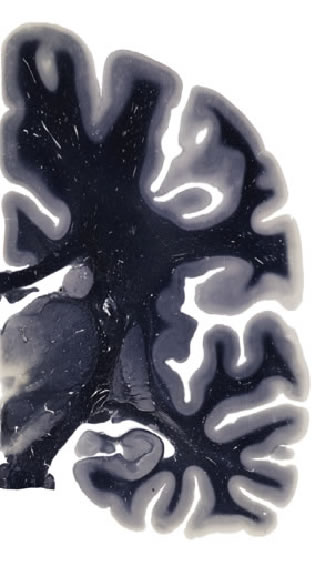

Hi-Resolution Sections · Cells (Nissl Staining) · Virtual Microscopy

Frontal sections (Nissl) from the Atlas Brain:

Slice ID:

r3-0649

Plate NR:

37

Position:

19,9 mm